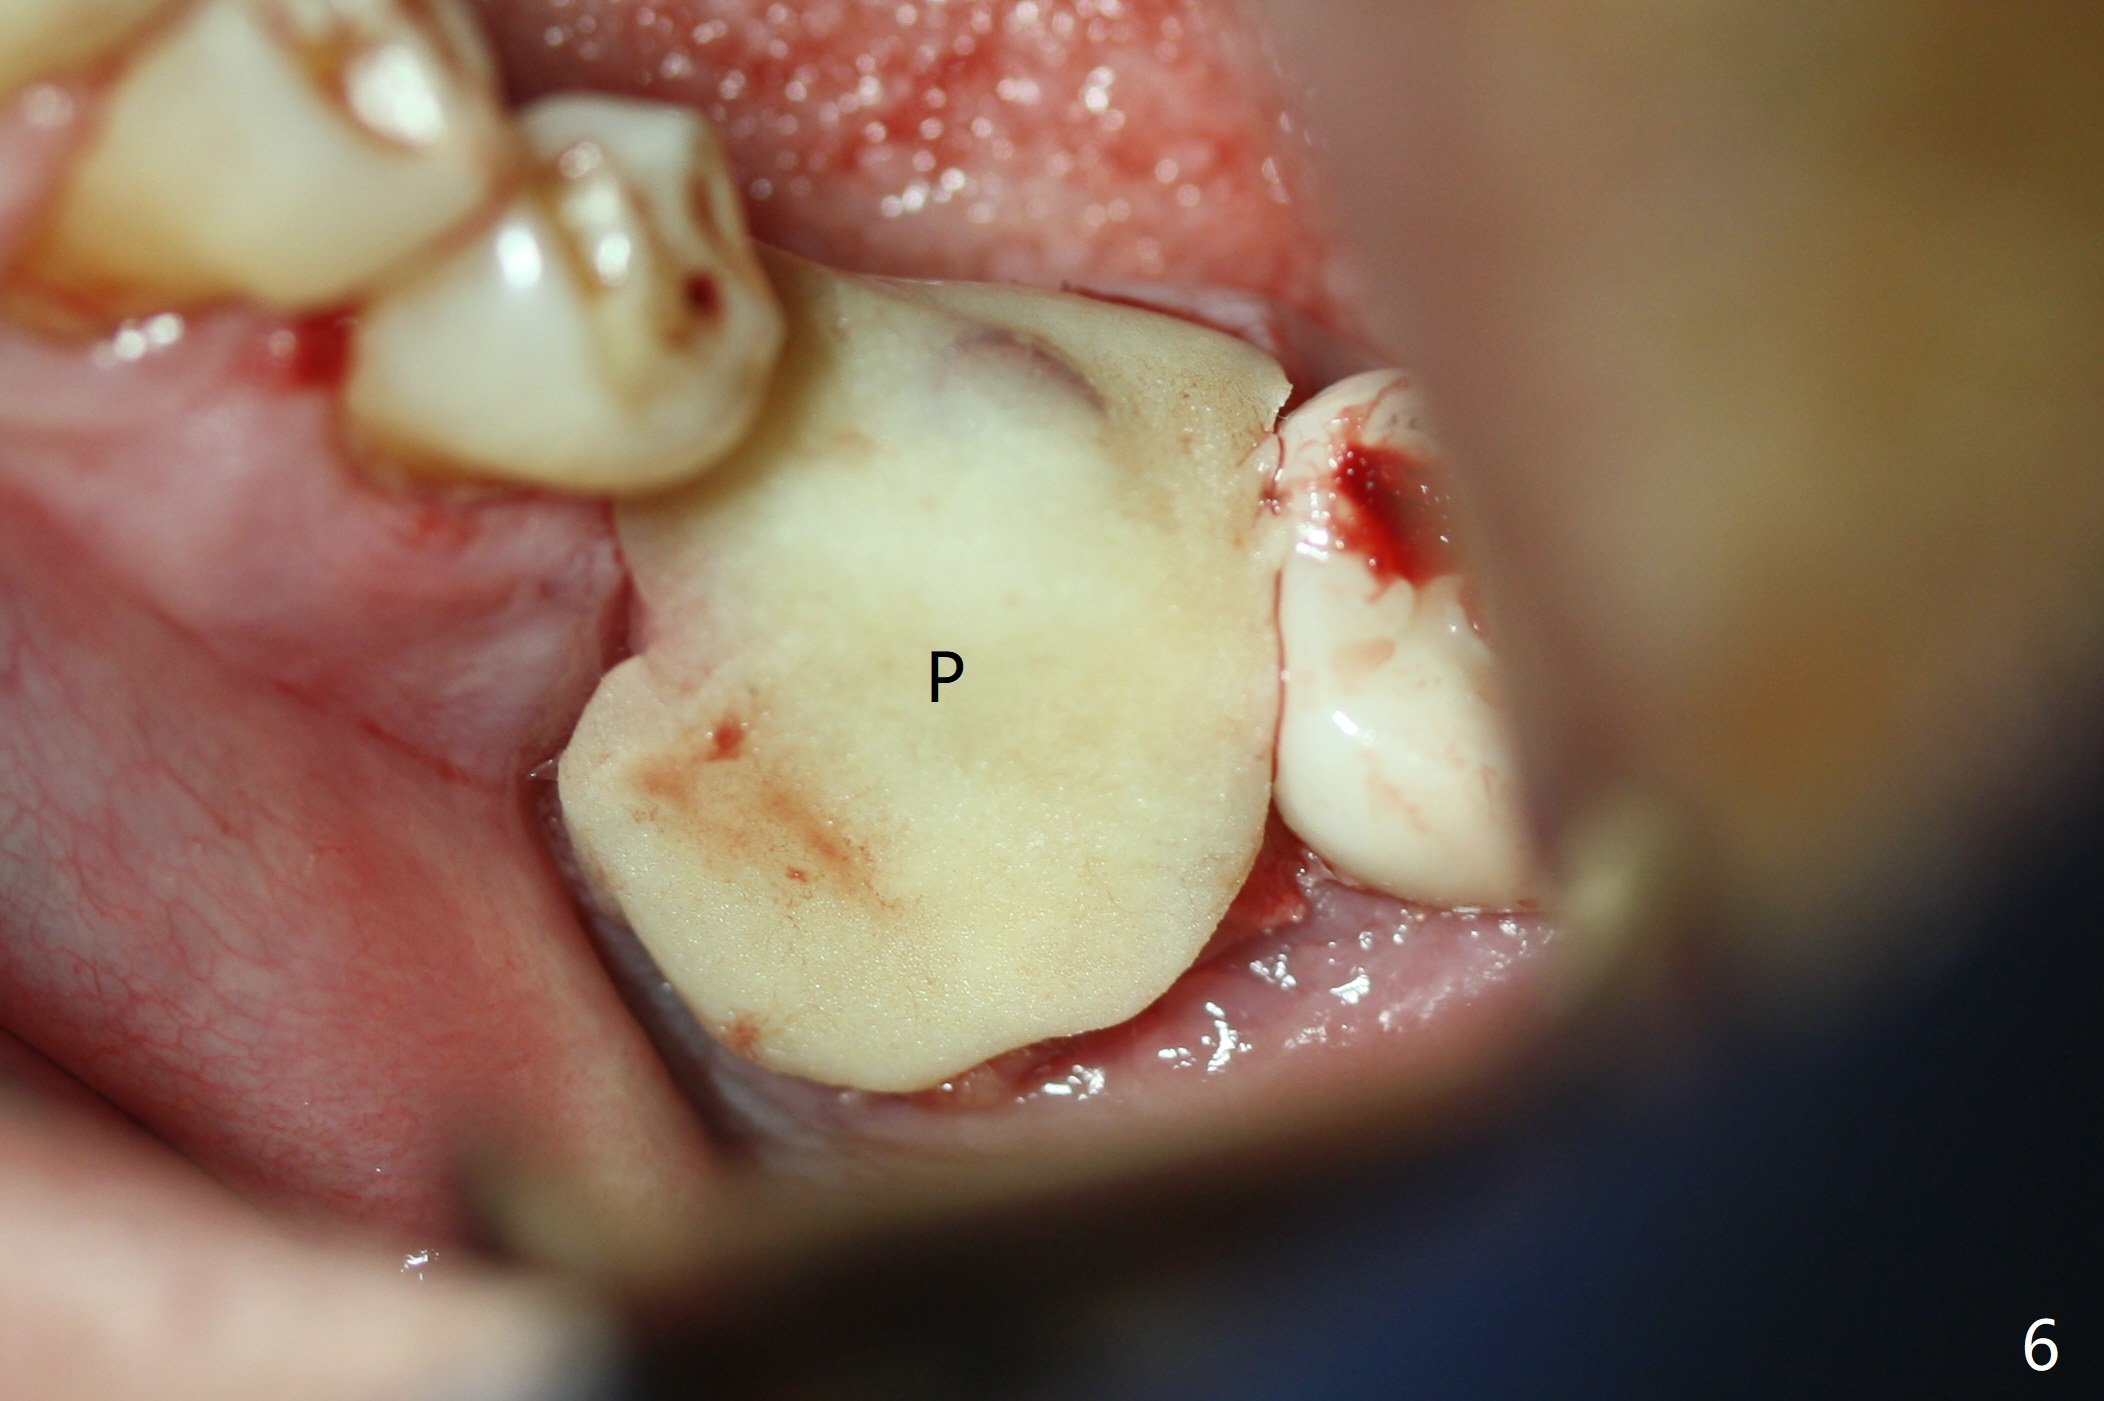

Probably due to severe infection at #19, pain control is difficult. Osteotomy has to be stopped 1.5 mm short of the design. PA taken with a 4.5x10 mm dummy implant does not show the Inferior Alveolar Canal (Fig.1), whereas CT does (Fig.2). With 6 mm clearance, block anesthesia is administered. A 5x10 mm definitive implant is placed with ease (Fig.3). The buccal bony defect is repaired by allograft (Fig.3,4 *), while the soft one by 3 pieces of PRF membrane (Fig.5). The latter is fixed in place by applying setting acrylic as an immediate provisional (Fig.6 P) over the wound, around the abutment (A) and locking into the undercut of the neighboring tooth/implant crown. The patient feels great postop. The gingiva is healthy around the provisional 8 days postop (Fig.7). The patient remains asymptomatic with the healthier gingiva surrounding the simplified provisional 22 days postop, as compared to 8 days postop (Fig.8). The socket heals when the simplified provisional is removed 1.5 months postop (Fig.9-12). The bone graft (Fig.11 ^) seems to have become a part of the regenerated gingiva. The abutment has been dislodged for 2 week (Fig.14 (3 months postop). The bone graft, albeit decreased, is 2 mm subgingival (red dashed line). There is bone distal to the implant 11 months postop (Fig.15 *). There is no bone loss 2 years postop; the UF abutment is completely seated (Fig.16).